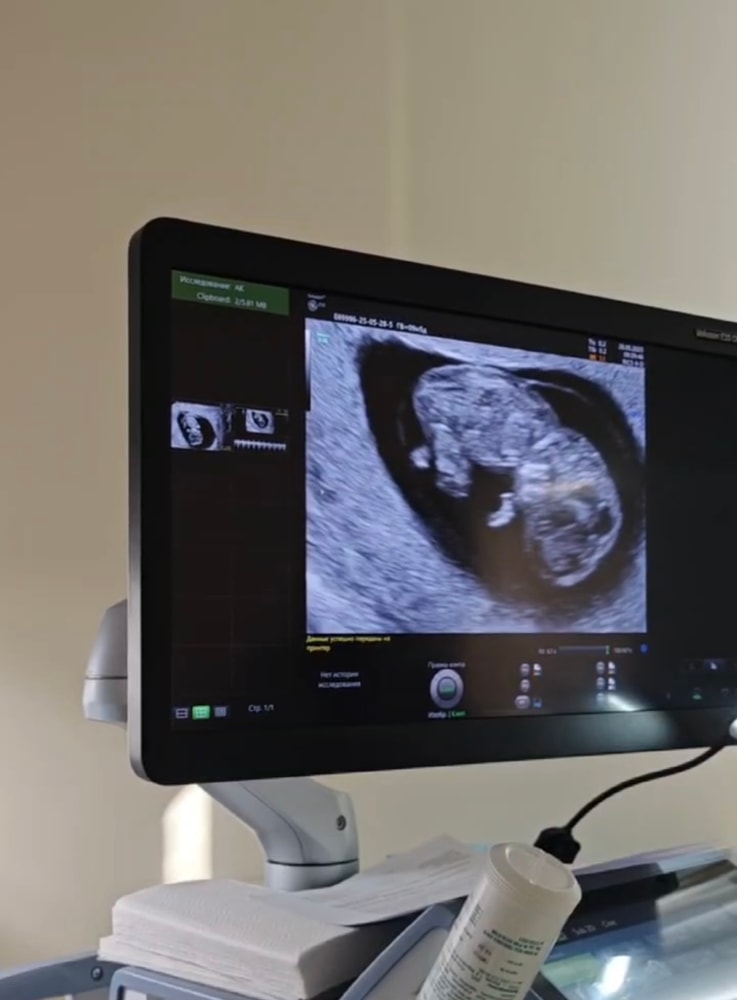

УЗИ 10 недель

На УЗИ все прошло замечательно. Малыш развивается, и опережаем по срокам, уже не на 2 дня как было пару недель назад, а на 5 дней. Когда мы начали проводить УЗИ, малыш еще спал..а потом бац и резко проснулся. Начал трясти ручками и ножками, дрыгался так прикольно😂 Хорошо были видны пяточки, ручки и ножки. В мозгу уже образовались 2 полушария. Позвоночник тоже показали. С моего лица просто не сходила улыбка от радости.

По параметрам малыша, срок ровно 10 недель:

Плодное яйцо: 46*39*45мм

КТР: 30,7мм

ЖМ: 4,5мм

Сердцебиение: 174 уд в мин

Толщина хориона: 11,2мм